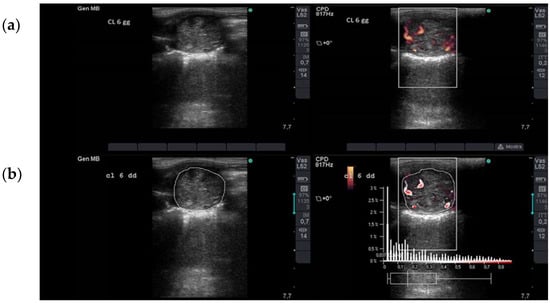

2.2. Ultrasonographic Assessment of Luteal Blood Flow